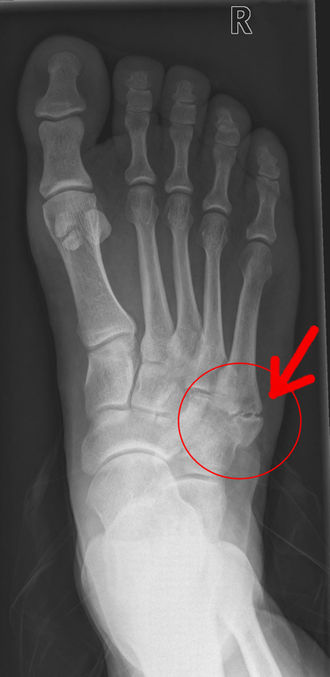

Al examen físico se encuentra dolor a la palpación de la base del quinto metatarsiano. La radiografía es esencial para hacer diagnóstico diferencial con otras Patologías 🤔🤔. Es importante no confundir con una fractura,ni con una enfermedad congénita llamada os vesalianum. Para eso hay que hacer un examen físico cuidadoso y radiografía.

¿Qué es Os Vesalianum ?

Es una enfermedad congénita en la que el tendón del peroneo tiene un hueso sesamoideo, que puede parecer una fractura o un caso de Iselin.